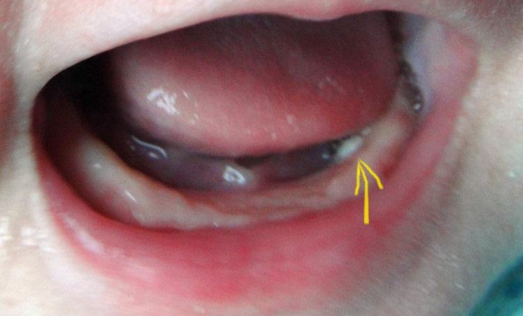

鵝口瘡,不是馬牙,新生兒患的鵝口瘡是由于白色念珠菌感染造成的皮膚損害,通常在牙齦周圍形成,有斑片狀白膜附著,用棉簽可輕輕剝?nèi)ァ內(nèi)グ咨つず螅撞砍溲黠@。

口腔內(nèi)粘膜出現(xiàn)白色斑塊,可以用棉簽或舌壓板用力擦去斑膜,露出下面的紅肉,一定要和奶瓣區(qū)別開來,鵝口瘡的白斑不易擦掉,吃奶時嬰兒不易裹嘴,或不吃奶,病變可蔓延到咽部食管,唱到,氣管,肺,有先天免疫缺陷的也有彌漫性感染。